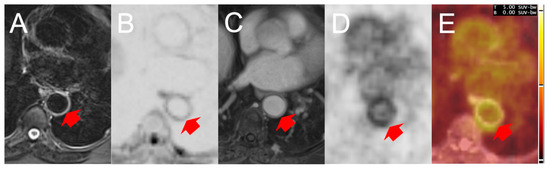

3.2. MRI Findings Compared to PET/CT and Ultrasound in the Axillary Segments

3.3. MRI Findings Compared to PET/CT in the Thoracic Aorta